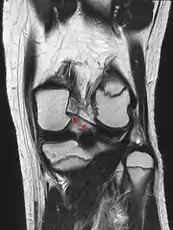

Posterior meniscofemoral ligament on MRI, coronal

Posterior meniscofemoral ligament (Wrisberg) behind the posterior horn of the lateral meniscus close to its insertion. Sometimes wrongly interpreted as a meniscal tear.